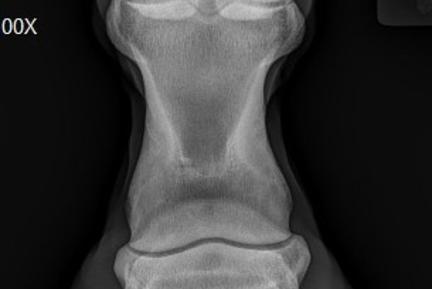

Radiology or x-ray imaging is the backbone of all imaging modalities in any sport horse practice. X-rays are relatively large radioactive particles that are produced and fired from an x-ray generator. They then travel through a body part or area and to a plate containing x-ray sensitive receptors or crystals, ultimately producing the typical black and white x-ray image. The days of toting bags full of cassettes back to a clinic for development in a dark room and finally looking at the film when backlit on a large view box have given way to Direct Digital Radiology (DDR) imaging solutions. Today, practitioners have almost immediate (4-12 seconds) viewing of high quality images. Yet much about radiology remains the same; it is still a one dimensional image, and only 4 different densities can reliably be distinguished. Since the image is one dimensional, multiple views taken while circling around the body part is best. A complete study of the distal limbs for example would require at minimum of 4 views. Some areas however, the shoulder for example, allow for only one view. The different densities that radiology allows us to “see” are bone/mineral, soft tissue, fat, and air. With today's software-enhanced images, however we can “see” different soft tissue densities such as the tendons and ligaments, and the sensitive laminae in the hoof.

Throughout my practice career I have been obsessed with high quality x-ray imaging. Today, my equipment, made by Cannon, is totally wireless and has the fastest image process time currently available in equine practice. Without superior imaging equipment and experienced interpretation of the images, difficult diagnoses may remain elusive. I have always understood this and am committed to continuing to be a leader in equine radiology.